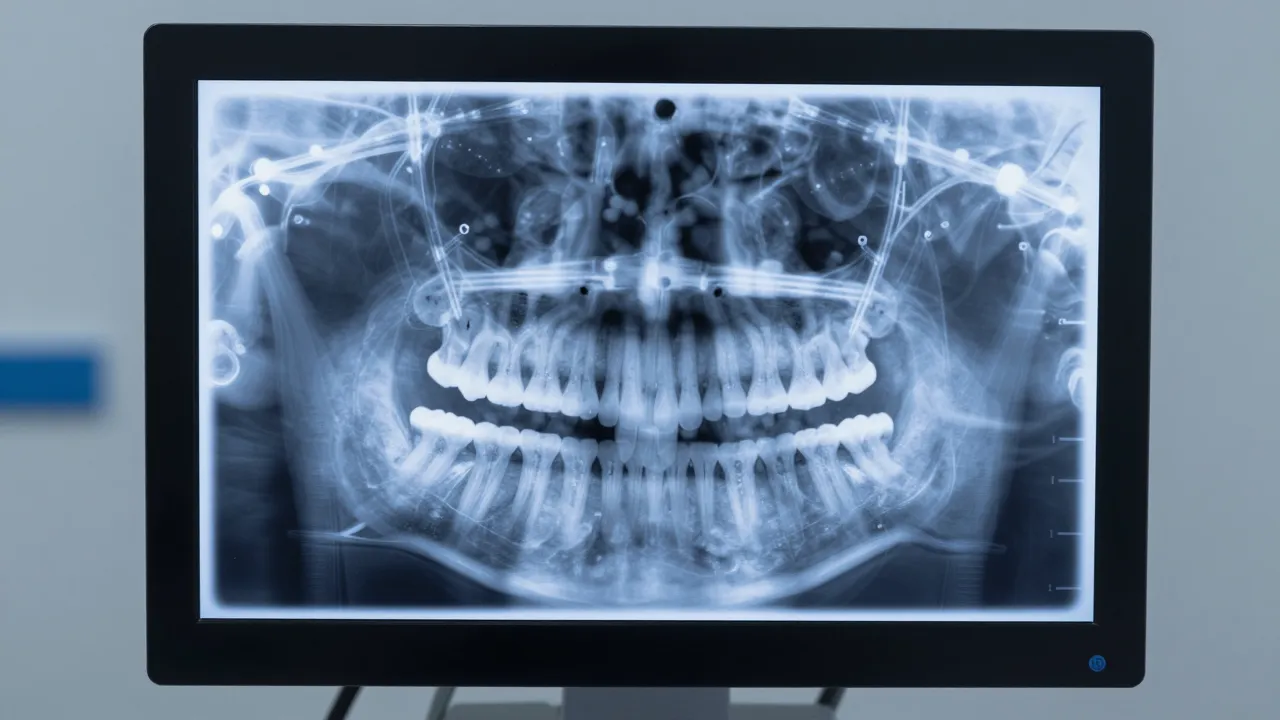

치아 건강을 위해 가장 중요한 것은 '진단의 정확성'입니다. 365열린치과를 찾는 환자들이 가장 만족해하는 부분 중 하나는 바로 시각적인 설명이에요. 말로만 듣는 설명은 늘 반신반의하기 쉽지만, 디지털 영상 자료를 통해 자신의 치아 상태를 직접 눈으로 확인하면 상황은 달라집니다.

- 디지털 정밀 진단 장비: 눈으로 보이지 않는 치아 뿌리까지 명확하게 보여주는 장비가 구비되어 있는지 확인하세요.